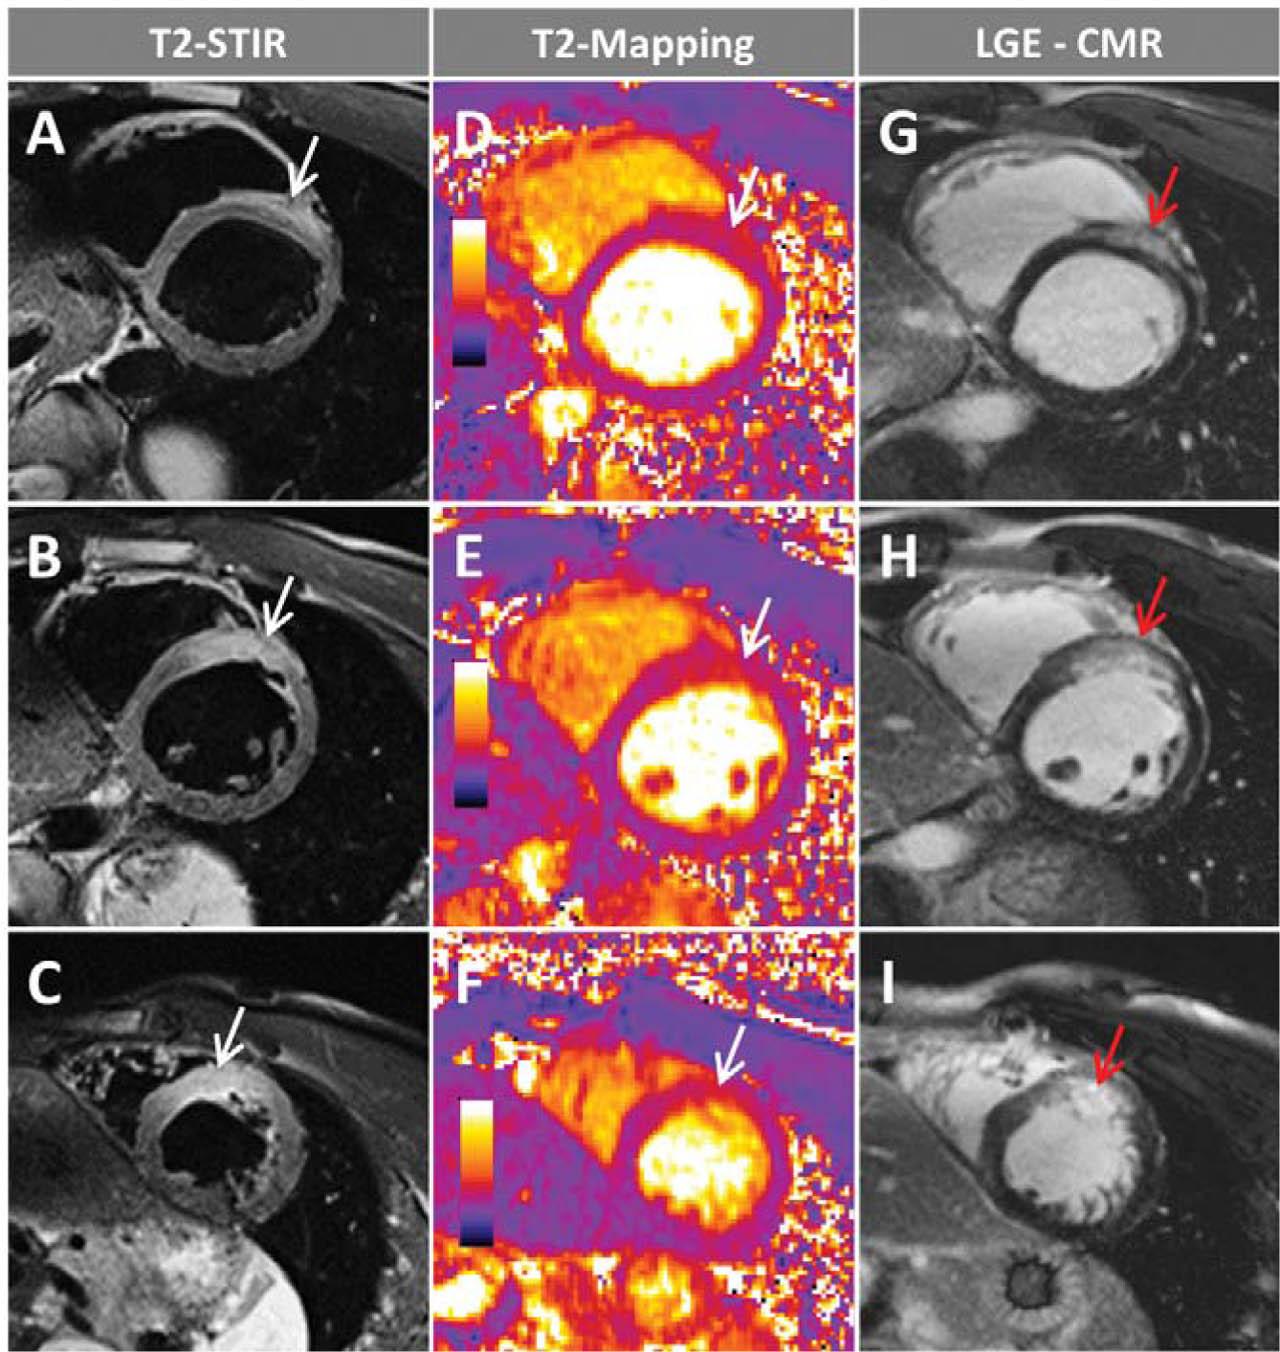

Figure 4

Edema sensitive T2-STIR (A, B, C) and T2-Mapping images (D, E, F) as well as LGE images (G, H, I) in a patient with acute anterior myocardial infarction. Acute ischemic myocardial damage in the anteroseptal and anterior myocardial segments can be seen with edema (white arrows): transmural T2-hyperintesity (A, B, C) and corresponding elevated T2 times (D, E, F), together with subendocardial to transmural LGE (G, H, I, red arrows).